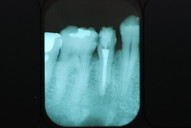

必ずばい菌が侵入しないようにしてばい菌である虫歯を除去します。

銀歯の下はばい菌だらけです。こういうのはよくあります。取り残しですね。![treatment_05[1]](https://livedoor.blogimg.jp/netdental/imgs/3/a/3ad019d0-s.jpg)